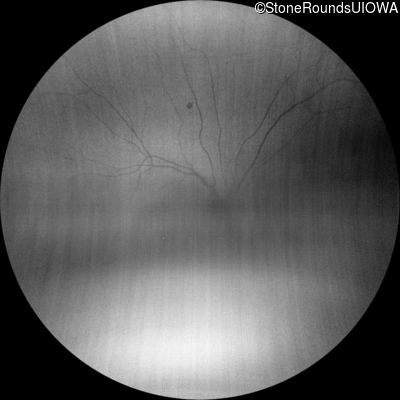

Infrared Fundus Photograph - Right - 10/125 -1

Exemplar

Infrared Fundus Photograph - Left - 10/100 -1